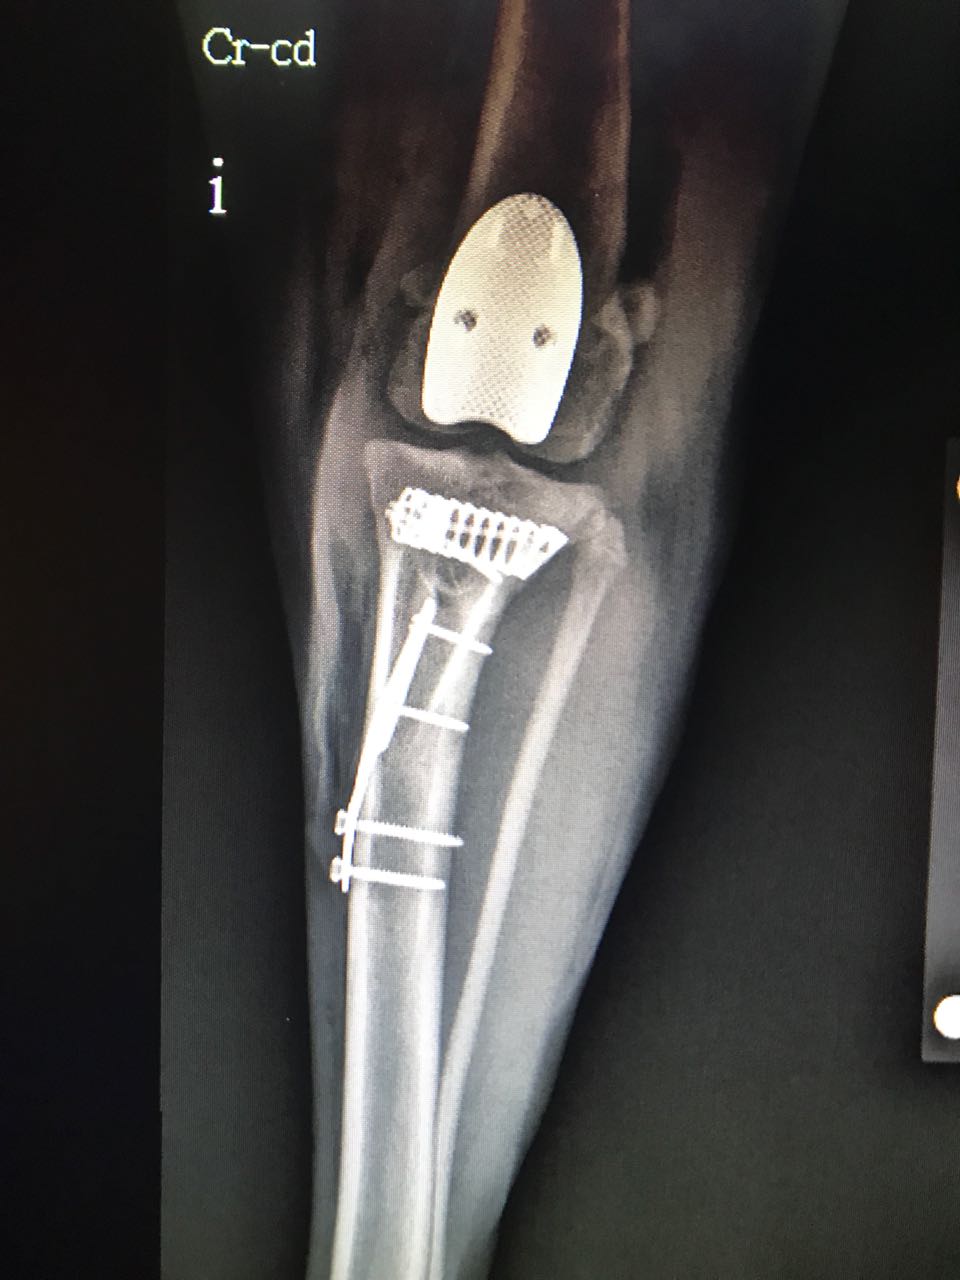

Beremiz Sánchez, encontró que Chavy presentaba luxación patelar grado IV -es decir que su rótula salió del surco de la rodilla-, y como consecuencia de ello sufrió desalineación del músculo cuadricep desarrollando a lo largo del tiempo una enfermedad degenerativa severa en su rodilla.

Además presentaba, ruptura del ligamento cruzado craneal, condición muy común en caso de luxación patelar y que predispuso a una mayor inestabilidad e inflamación articular.

El especialista detalló que el procedimiento a efectuarse era colocar un surco protésico para mejorar su condición biomecánica y contrarestar el dolor.

El procedimiento fue realizar el reemplazo del surco troclear PGR (patellar group replacement). “Se reemplazó el surco degenerado por una prótesis de titanio extra pulido o ultra pulido. Esta prótesis lo que busca es tener una superficie articular sumamente lisa para evitar que haya un roce inadecuado entre la rótula y la superficie articular degenerada”, indicó el especialista en ortopedia.